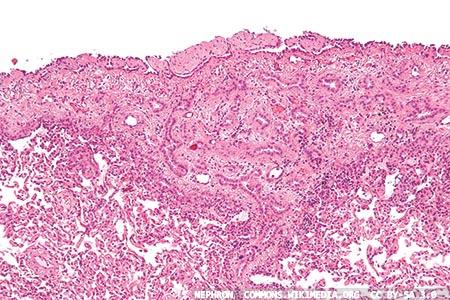

H E And Immunohistochemical Staining Of Meningioma And Mesothelioma Download Scientific Diagram

Histological Findings Of Patient With Bap1 Germline Mutation A Liver Download Scientific Diagram